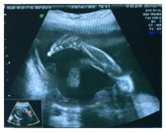

03/18/15- Ultrasound monitoring at 27 weeks of gestation where described the previous thoraco-abdominal wall protrusion 4cm with visceral and cardiac mass (Figure 1) with pericardial effusion and ventricular septal defect, umbilical cord with 6.4 cm in length (Figure 2), direct fetal placental implantation, it is assumed therefore decreased fetal movement, placenta posterior fundus grade II, face seen unchanged (Figure 3), no abnormalities in upper and lower limbs (Figure 4), amniotic fluid index 35cm concludes: Pregnancy of 27 weeks and body stalk anomaly.3,4

Figure 1 Ultrasound monitoring at 27 weeks of gestation where described the previous thoraco-abdominal wall protrusion 4cm with visceral and cardiac mass.

Figure 2 Ultrasound monitoring at 27 weeks of gestation with pericardial effusion and ventricular septal defect, umbilical cord with 6.4 cm in length.

Figure 3 Ultrasound monitoring at 27 weeks of gestation direct fetal placental implantation, it is assumed therefore decreased fetal movement, placenta posterior fundus grade II, face seen unchanged.

Figure 4 Ultrasound monitoring at 27 weeks of gestation with no abnormalities in upper and lower limbs.